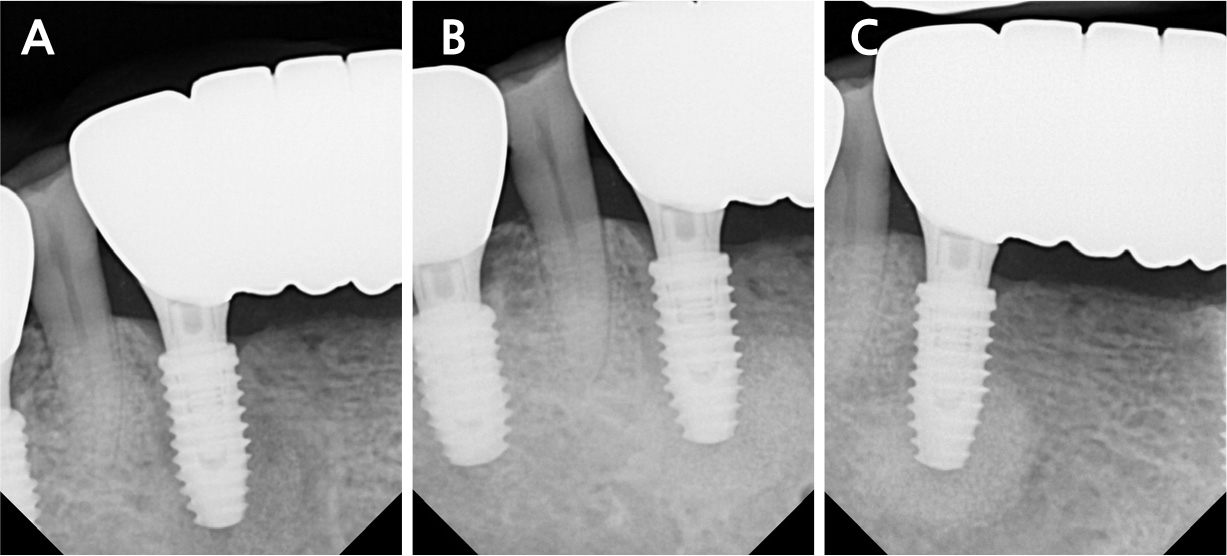

All surgical procedures were performed under local infiltration anesthesia using 2% lidocaine with 1:80,000 epinephrine. Fig. 3A shows the preoperative view. A horizontal incision with a vertical releasing incision at the distal end was made, including one or two adjacent tooth/implant crowns at the mucogingival junction (MGJ), using a #15c blade (Fig. 3B). Following mucoperiosteal flap elevation, the buccal fenestration (Fig. 3C) was apically expanded to approximately ∅5 mm circular window using a diamond drill from a sinus floor elevation kit (DASK Simple kit; Dentium, Suwon, Korea). Granulation tissue was detached and debrided using a surgical curette and hand instruments from the DASK Simple kit (Fig. 3D). The implant surface was decontaminated with a titanium brush (TN brush; Dentium) at 800 rpm under saline irrigation, followed by scrubbing with a cotton pellet soaked in tetracycline hydrochloride for 2 min (Fig. 3E and 3F). The peri-implant bone defect was filled with deproteinized porcine bone mineral (Osteon Xeno; Dentium) and covered with a porcine collagen membrane (Collagen Membrane II; Dentium) (Fig. 3G and 3H). Interrupted sutures were placed using a 6–0 monofilament nylon thread (Ethilon; Ethicon, Somerville, United States) to stabilize the wound (Fig. 3I). The patient was advised to avoid mechanical plaque control at the surgical site and to rinse twice daily with an antiseptic mouthwash (GUM dental rinse; Sunstar, Etoy, Switzerland) for 2 weeks. Antibiotics (clindamycin 150 mg, three tablets daily) and an analgesic (acetaminophen 600 mg, three tablets daily) were prescribed for 5 days to manage postoperative infection and pain. Symptoms resolved following surgery. The wound showed secondary healing at suture removal (2 weeks after surgery) and was fully closed by 4 weeks (Fig. 4). Radiographic bone fill was maintained at the 1.5-year follow-up (Fig. 5).